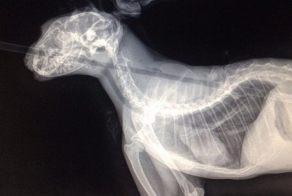

Неловкий котэ не смог пролезть в створки открытого на проветривание окна. Хорошо, что на помощь бедолаге скоро пришли. Правда, не смогли удержаться, чтобы предварительно не сфотать горемыку.